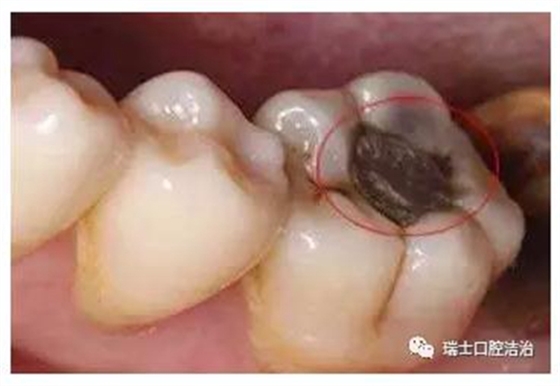

齲齒就是齲病、蛀牙、蟲牙或者爛牙。一說齲齒,大家立馬會想起兒童的專屬牙病,其實齲齒的發(fā)病率非常高,不單單是兒童,幾乎每個人都有不同程度的齲齒。不過,我們今天關注的是我國兒童的齲齒情況。

根據(jù)衛(wèi)計委最新公布數(shù)據(jù),我國12歲兒童恒牙齲患率為34.5%,比十年前上升了7.8個百分點。5歲兒童乳牙齲患率為70.9%,比十年前上升了5.8個百分點。農(nóng)村高于城市。兒童患齲情況已呈現(xiàn)上升態(tài)勢。

齲齒對兒童牙齒的損害不容忽視,國際上已經(jīng)將齲齒、腫瘤以及心血管疾病列為危害人類健康的三大疾病。齲齒是牙齒在多種因素影響下,牙硬組織脫礦、有機質(zhì)溶解、牙組織進行性破壞,導致牙齒缺損的常見疾病。

兒童作為預防齲齒的重點人群,家長必須引起足夠的重視。家長要隨時留意孩子的牙齒情況,尤其是后磨牙,比如孩子的第一顆恒牙六齡齒(下頜)就是很容易發(fā)生齲齒的牙齒。一旦發(fā)現(xiàn)齲齒,就必須及時治療,不要心存僥幸,也不能輕視齲齒的破壞力。齲齒可完全破壞整個牙冠,僅殘留半截壓根暴露在外,黑乎乎的很是嚇人。